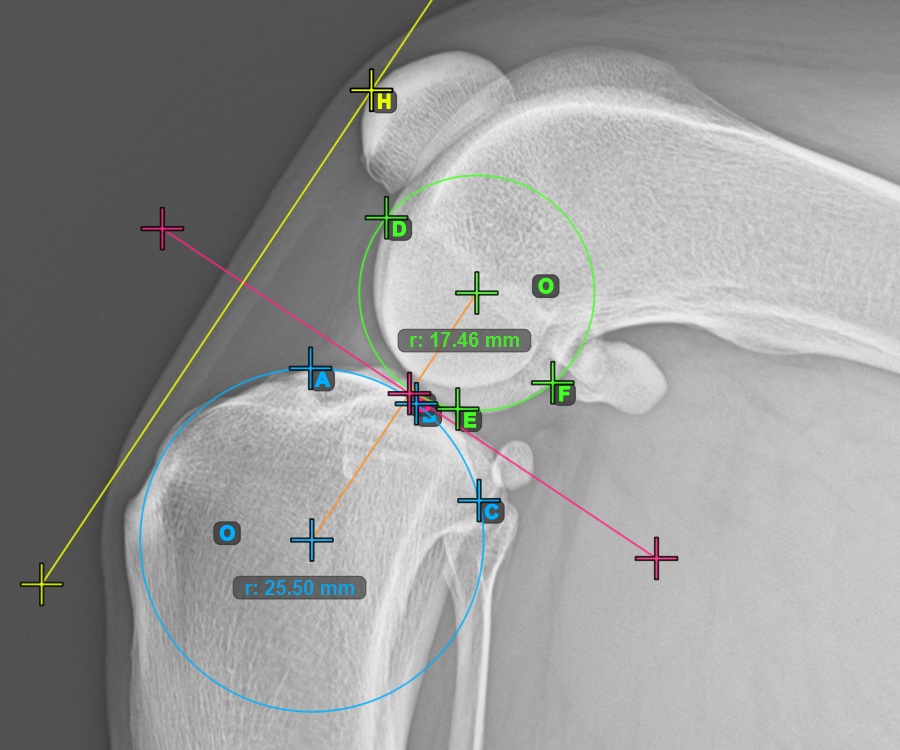

Fahren Sie fort, indem Sie die drei Punkte auf der Gelenkfläche des Condylus Femoris markieren.

Markieren Sie die drei Punkte am Hauptkondylus des Oberschenkelknochens (Condylus Femoris). Unabhängig von der Reihenfolge stellen Sie sicher, dass Sie den vordersten Punkt, den hintersten Punkt und den Mittelpunkt des Condylus Femoris markieren. Basierend auf den drei gesetzten Punkten wird automatisch ein Kreis konstruiert.

Das Bild unten zeigt die typische Platzierung der drei Punkte am Condylus Femoris.